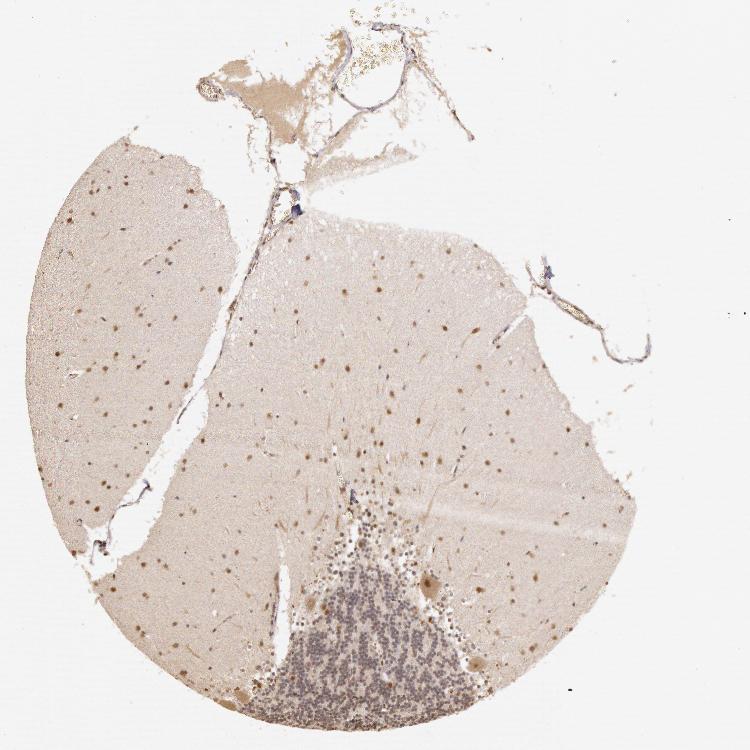

CEREBELLUM - Antibody stainingi

Antibody staining in the annotated cell types in the current human tissue is reported as not detected, low, medium, or high, based on conventional immunohistochemistry profiling in selected tissues. This score is based on the combination of the staining intensity and fraction of stained cells.

Each image is clickable and will lead to virtual microscopy that enables deeper exploration of all samples and also displays staining intensity scores, fraction scores and subcellular localization as well as patient and tissue information for each sample.

Antibody HPA001334

Purkinje cells Medium

Cells in granular layer Low

Cells in molecular layer Medium